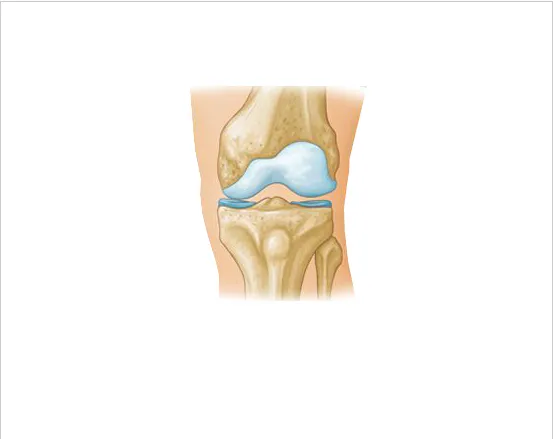

두 번째는 연골 손상

무릎 관절 사이에서 뼈와 뼈의 마찰을 줄여주는 부드러운 조직인 연골이 관련되어 있습니다. 나이 증가, 과체중, 관절염 등으로 인해 연골이 닳거나 소실되면, 뼈 사이의 직접적인 마찰로 인해 통증이 발생할 수 있으며, 이로 인해 움직임의 제한, 삐걱거리는 소리, 염증과 같은 증상이 나타날 수 있습니다.

이 상태의 치료는 체중 감량, 적절한 운동, 보조기 사용과 같은 자가 관리와 필요에 따라 진통제, 항염제, 보호주사, 관절경 수술 등의 의학적 치료를 포함할 수 있습니다.